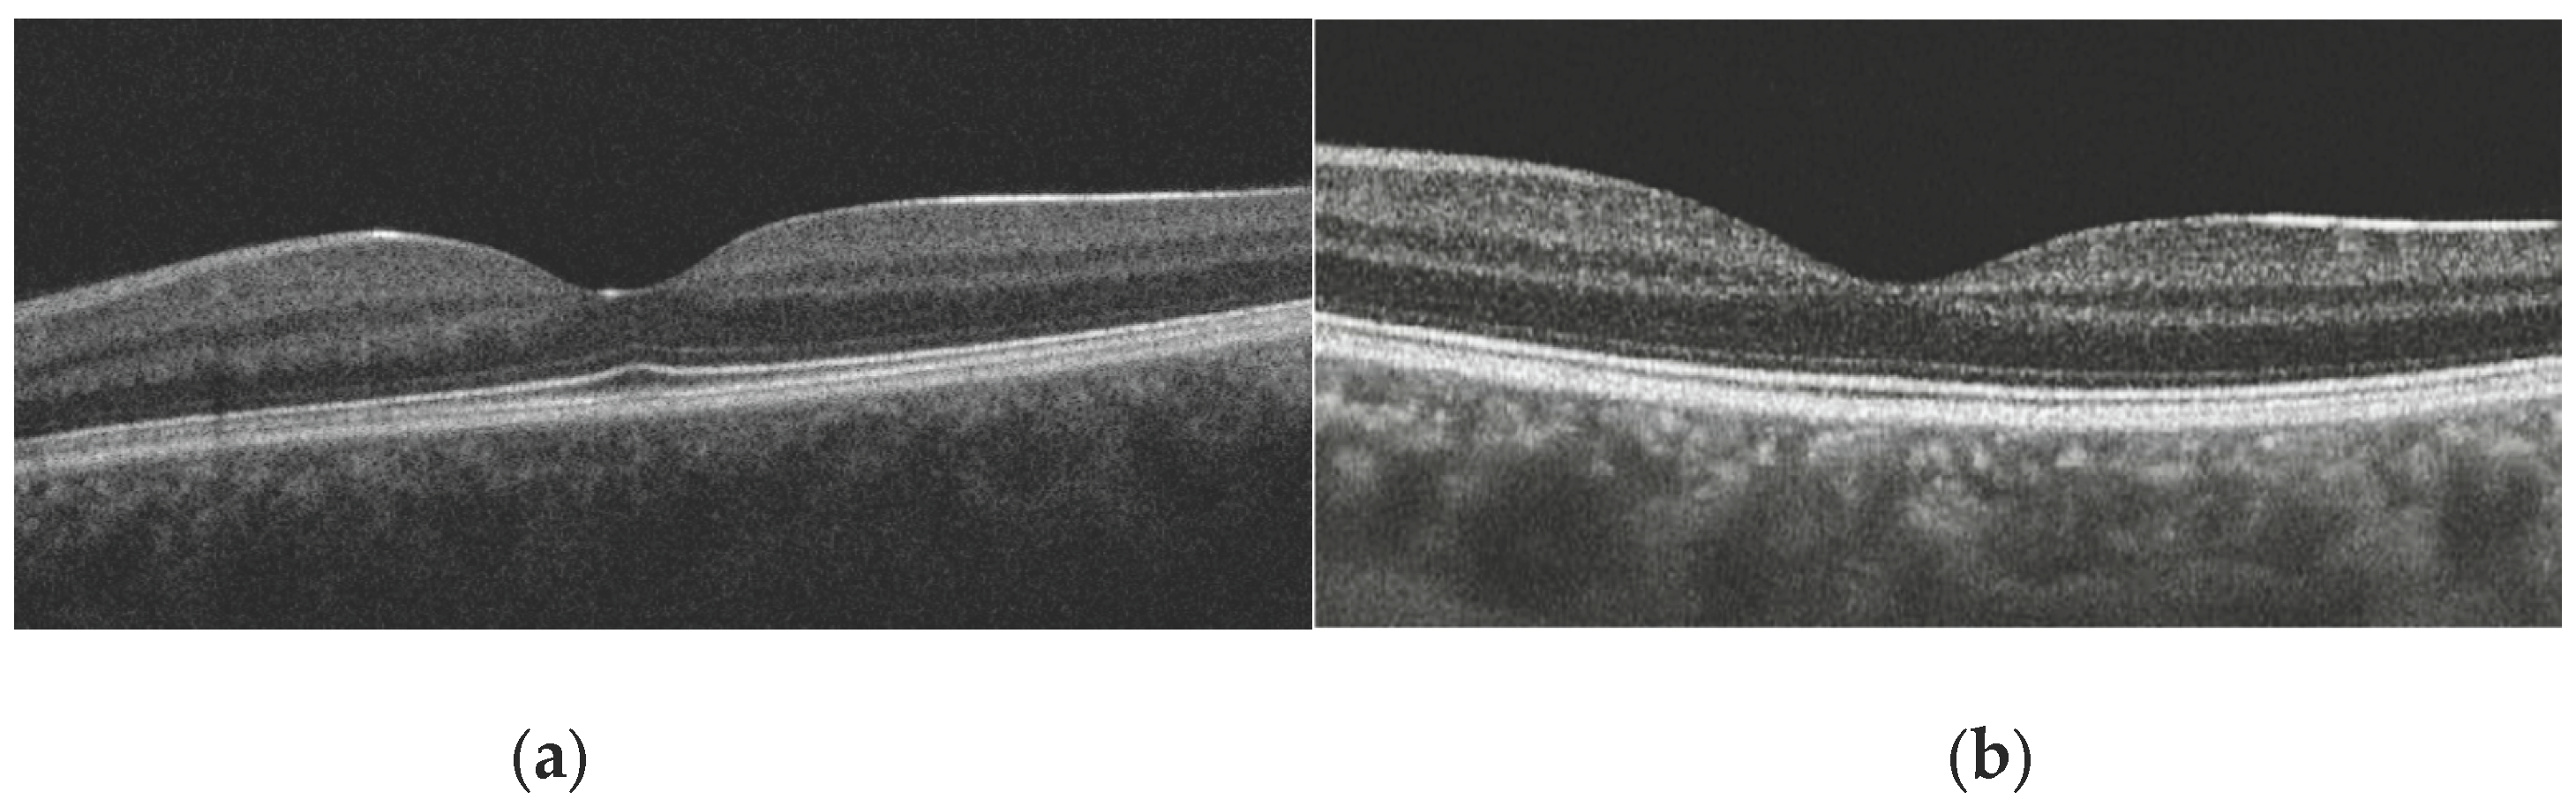

• Presence of Foveal Bulge: This was assessed visually by two independent graders on magnified B-scan tomograms passing through the foveal center (Figure 2a,b). The bulge was defined as a visible convexity (towards the vitreous) of the ellipsoid zone (EZ) line or the EZ-outer photoreceptor segment complex. In cases of disagreement (<2 % of cases), a joint discussion with a third senior expert was held for a final decision.

Figure 2. Representative swept-source OCT B-scans illustrating qualitative assessment of the foveal bulge. (a) Presence of the foveal bulge in healthy subjects, visible as a convexity of the ellipsoid zone or ellipsoid zone–outer photoreceptor segment complex at the foveal center; (b) Absence of the foveal bulge, characterized by a flattened ellipsoid zone profile at the foveal center.